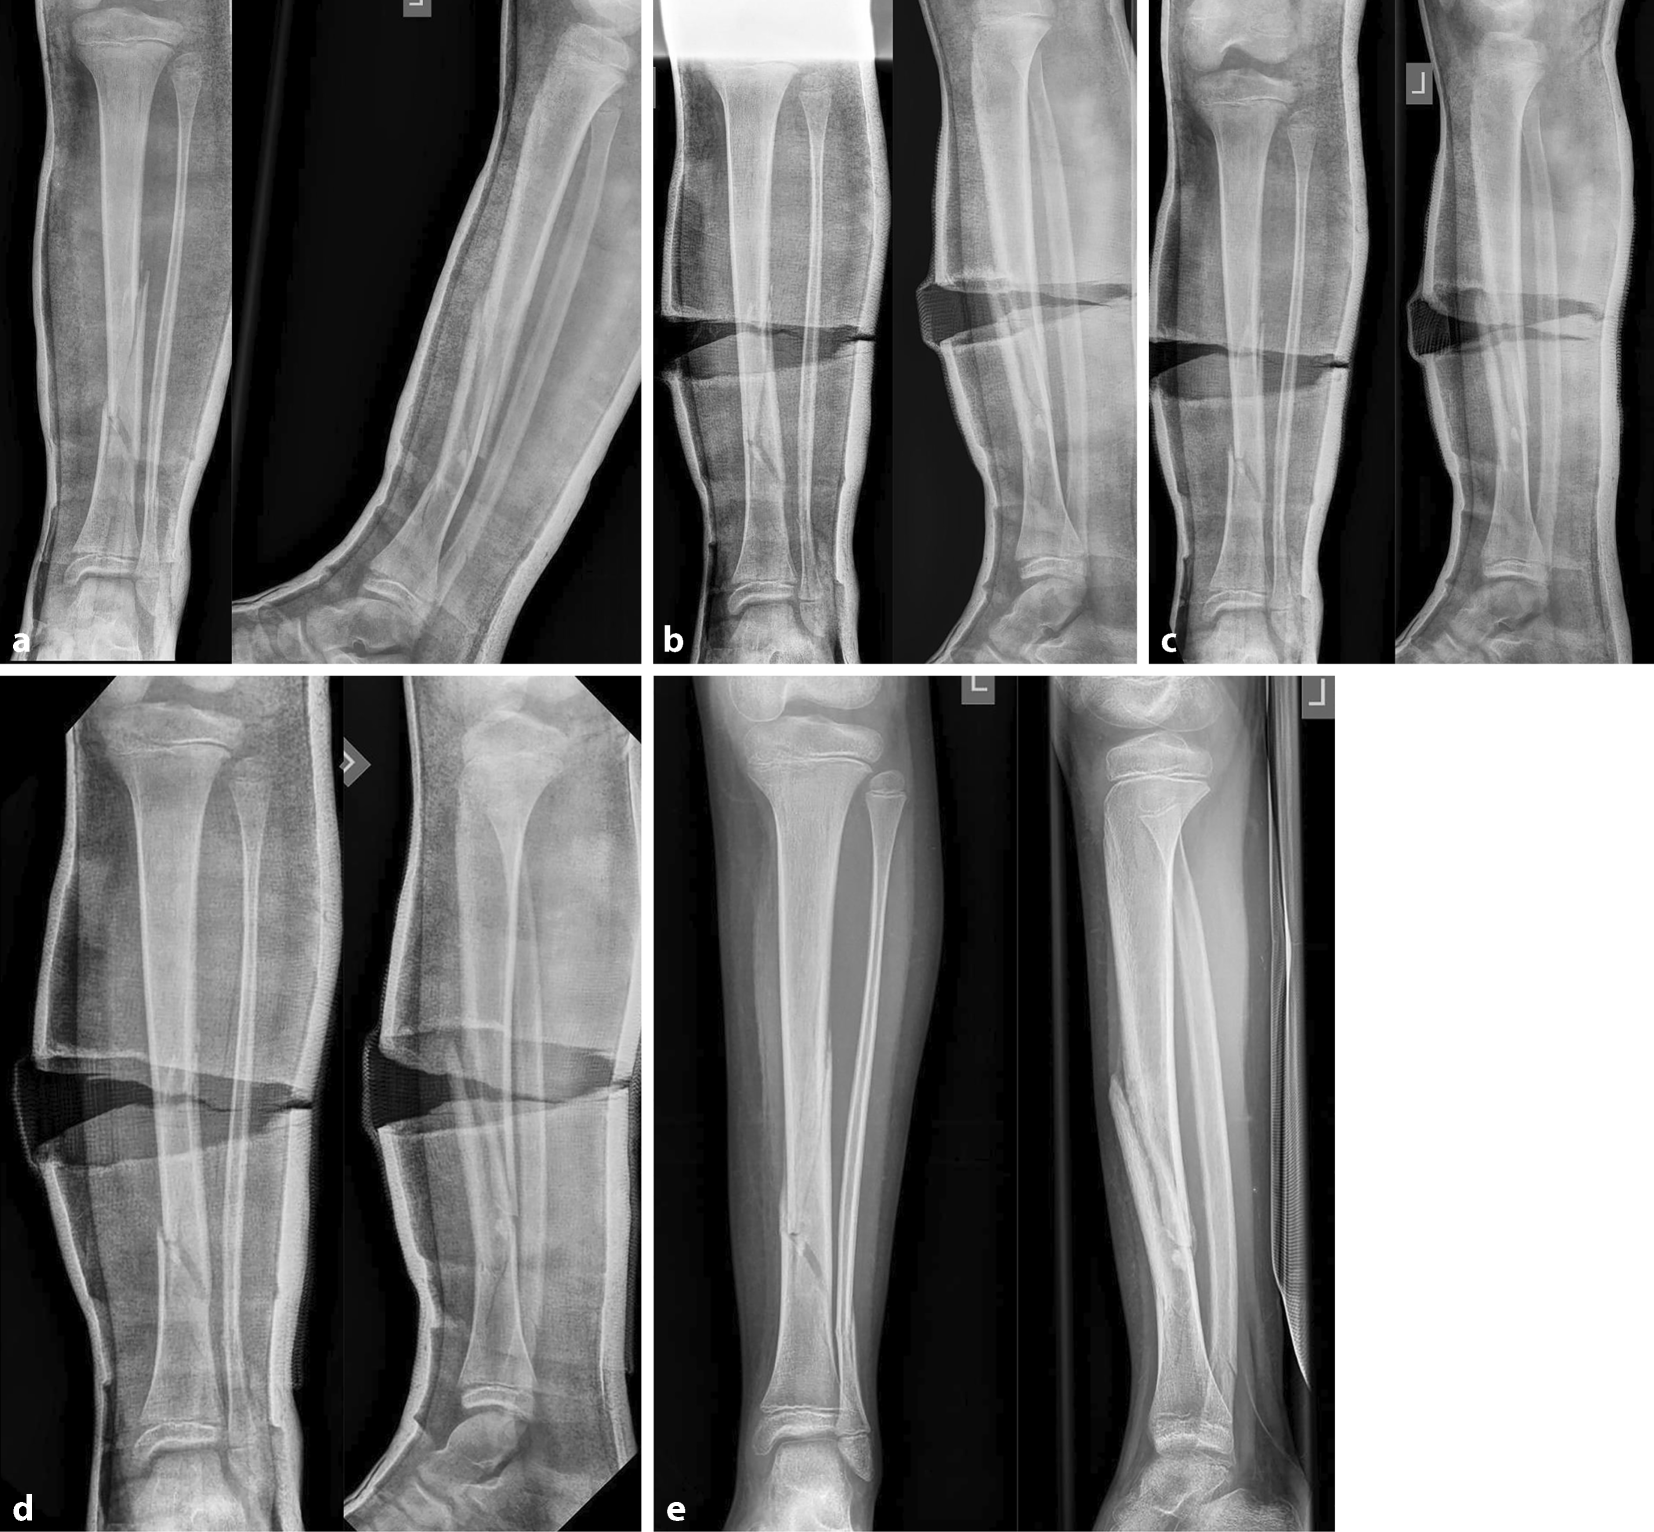

Abb. 21

Fallbeispiel Nachkeilung am Unterschenkel. 9‑jähriger Junge, Tibiaspiralfraktur mit ausgebrochenem ventralen Biegungskeil im mittleren und distalen Schaftdrittel, Achsenabweichung in den Varus und in die Retrokurvation, zusätzlich Grünholzkomponente an der Fibula (a). Am 8. Tag erfolgt die Beseitigung der Fehlstellung durch anteromediale Gipskeilung (b). Aufgrund des langstreckigen komplexen Frakturverlaufes wird nach einer Woche eine Stellungskontrolle durchgeführt, die eine diskrete Redislokation in den Varus zeigt (c). Die Kunststoffbinde wird entfernt, die Korrektur erfolgt durch weiteres Aufdehnen des Keilungsspaltes und Einlegen eines größeren Platzhalters (d), das Konsolidierungsröntgen nach 5 Wochen zeigt eine achsengerechte Ausheilung (e)